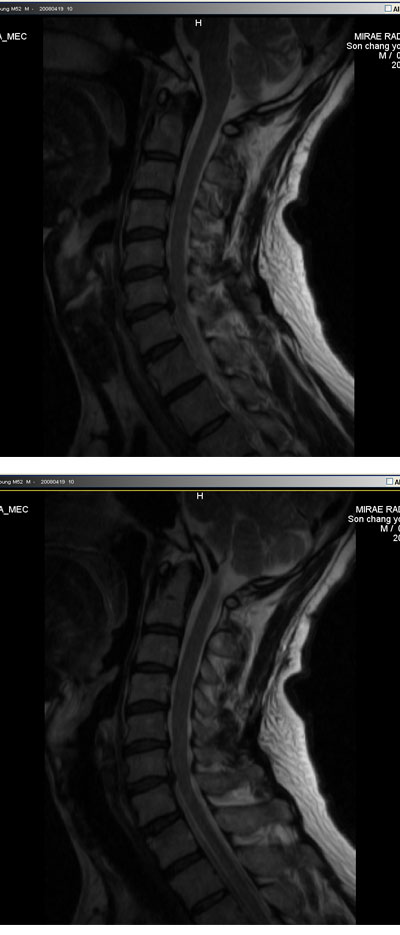

ǥغ no 3103 date 2008-05-16 16:54:22 hits 14 name â (soncy@pknu.ac.kr) IP: 210.125.108.52 鼭 ϻȰ ϴµ ־ ׳ ˻ϴ ǿ ũ ġḦ Ѵٰ Ͽ ħ ġḦ 2 Ͽ ٽ ܰ MRA ϶ Ͽϴ. ġḦ ϸ ٰ ǻ缱Ե ־ ġḦ ϰ ϴ ŭ ġ ʾ ٽ ͳ ˻ϴ ǥغ е ȿ ִٴ ʰ ־ ֹ ϰ Ǿϴ. ǥغ ֹ , ڼ ϴ ڼ 뿡 ϻȰ ״ Ͽ ڿ ϴ. ݾ 20 ϴ ̶ δٴ ° ϸ ־ ٰ ˴ϴ. ũ ؼ ϰ ô е鲲 ũ ġϿٴ ̾߱ Դϴ. ϴ ̳ ƮĪ ڱ ٵ ʿѰ ϴ. ũ ø . ° ȣ Դϴ. Ұ ۺ http://3wboard.zicoree.com/New_Board/Board/Read.php?Page=1&dummy=1210946870&Board=compill-50-free1&No=3103&Search=&keyword=&period=10000 --------- Խ ȣϽ Դϴ.------------- â* ũ ŷе mri (ֹȣ : 4ee6c7e9f04b ) ϼ е6 ߰ ͻ þȳ ŷе 0711 () ũ, 1C.ڵ, 1C., 1C.̸ , 1C.ڵӸ , 1C.ھ, 1C.ٱ (), 1C.߷ (), 1C.Ƿ (), 1C.ڱ ֺ , 4C.û°, 4C.5C.ھ, հ ̳ , 6C.ڸ , 6C. κ Ḳ , 6C.ھ Ḳ , 6C.ڻ , 6C.7C.ھ հ ̳ 7C.ڿʰ , 1T.ڼյ չٴ , 1T.ڼո , 1T.ڼհ ü ̳ , 1T. κ , 3T.ڵ , 2T. Ʒκ 4T. ȯ, 6T., 6T. Ű , 6T.ټ , 6T.ٽƮ 6T.ڼȭҷ 10T.ٸǷ, 4L.ڿ, 5L.ڹ߸̳ , 5L.ڹ ٸ ȯ, (). ڱô ũ(߰Ż), ũ(߰Ż)ġ, հ , , հ , ġ, , Ḳ , , Ḳ ġ Ǵ , , 㸮ũ(߰Ż) ߿ ġ , 㸮 ̳ ġ ߷, , нɷ , dz, , Ǵ ġ Ǻι̿, Ǻγȭ ָ, ָ, ָ Ǵ ġ ȭҷ ġ ͳ õ ͳ ˻ڷ õ http://3wboard.zicoree.com/New_Board/Board/Read.php?Page=1&dummy=1210946924&Board=compill-50-free1&No=3089&Search=&keyword=&period=10000 |